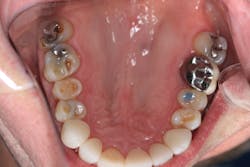

Radiographically, the first thing I noticed were the tabletopped occlusal surfaces (figures 1 and 2). Clinically, the same was evident, along with generalized wear facets on the posterior teeth (figures 3 and 4). The bite was deep (figures 5 and 6), and the lower anterior teeth had been worn down to half their original size. There were new ceramic crowns on nos. 21, 28, and 29. I also noted that there was an occlusal stop/resin on no. 13, but there was no significant effect on his occlusion as it was even on the right and left sides.